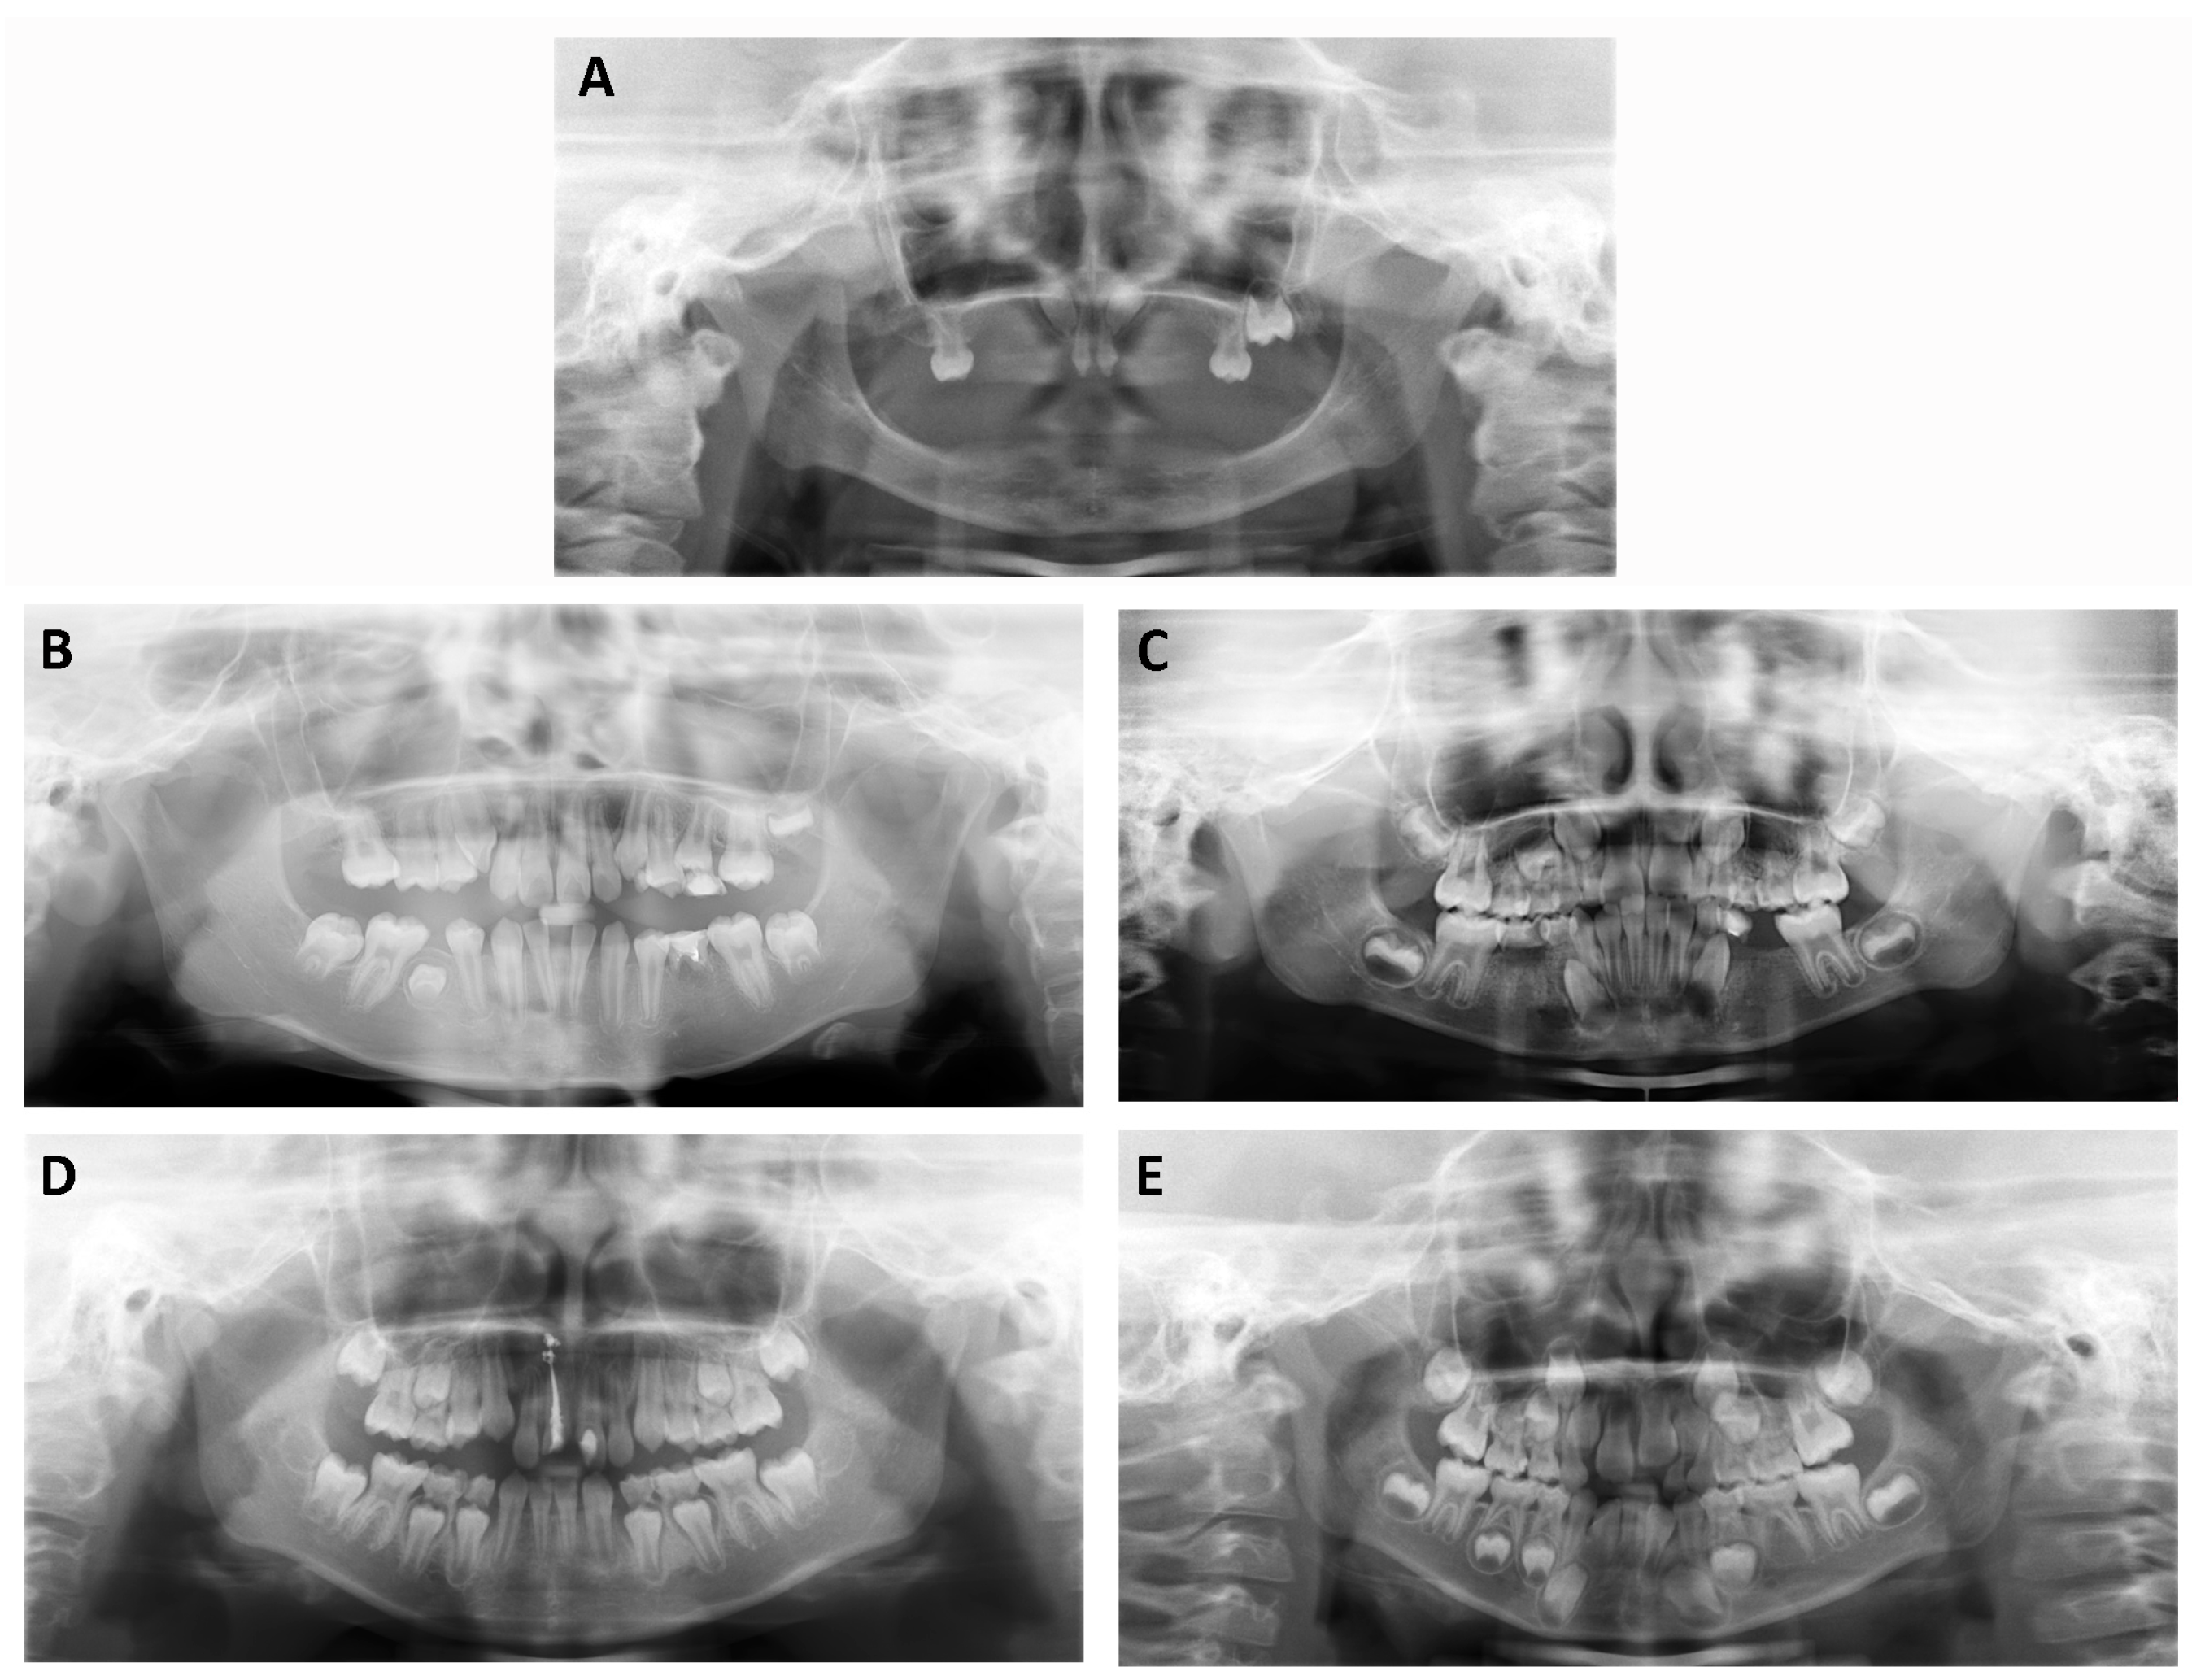

| Family | Patient | Age and Gender | Gene | Nucleotide Change | Amino Acid Change | Number of Missing Permanent Teeth # |

|---|---|---|---|---|---|---|

| XLHED1 | III:1 | 2y, M | EDA | c.1051G>T | p.Val351Phe | ND |

| XLHED2 | II:1 | 6y, M | EDA | c.467G>A | p.Arg156His | 23 |

| NSTA1 | II:2 | 10y, F | WNT10A | c.511C>T | p.Arg171Cys | 4 |

| NSTA2 | II:1 | 6y, F | WNT10A | c.742C>T | p.Arg248* | 9 |

| NSTA3 | II:1 | 9y, F | EDA | c.491A>C | p.Glu164Ala | 2 |

| NSTA4 | II:1 | 6y, F | EDAR | c.73C>T | p.Arg25* | 6 |

| Family | Patient | MT # | Right | Left | |||||||||||||||

|---|---|---|---|---|---|---|---|---|---|---|---|---|---|---|---|---|---|---|---|

| 8 | 7 | 6 | 5 | 4 | 3 | 2 | 1 | 1 | 2 | 3 | 4 | 5 | 6 | 7 | 8 | ||||

| XLHED2 | II:1 | 23 | Maxillary | * | * | * | * | * | * | * | * | * | * | * | |||||

| Mandibular | * | * | * | * | * | * | * | * | * | * | * | * | * | * | * | * | |||

| NSTA1 | II:2 | 4 | Maxillary | * | * | * | |||||||||||||

| Mandibular | * | * | * | * | * | ||||||||||||||

| NSTA2 | II:1 | 9 | Maxillary | * | * | * | * | * | * | * | |||||||||

| Mandibular | * | * | * | * | * | * | |||||||||||||

| NSTA3 | II:1 | 2 | Maxillary | * | * | ||||||||||||||

| Mandibular | * | * | * | * | |||||||||||||||

| NSTA4 | II:1 | 6 | Maxillary | * | * | * | * | * | |||||||||||